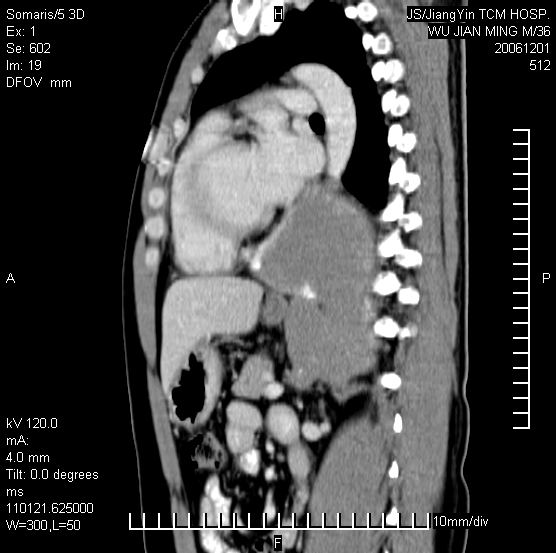

以下是引用dyqct在2006-12-1 21:17:00的发言:[br]左心缘旁及后肋膈窦区见巨大椭圆形混杂密度肿块,周围见大小不等斑片状钙化,内部无强化,周围包膜轻度强化,心脏明显受压变形,即明显占位效应,肿块广基与心包、膈相连。肝、脾内、肝门见多数小结节状钙化影。[br]考虑:1、左心缘旁及后肋膈窦区慢性包裹性胸膜炎(结核性);[br] 2、肝、脾及肝门淋巴结核已钙化。[br]

以下是引用zrs在2006-12-2 17:28:00的发言:[br]肺内、肝脾内虽有钙化,但不支持结核性胸胸膜炎包裹,而支持寄生虫感染![br][br]

以下是引用zyx168在2006-12-2 10:10:00的发言:[br][br]肝脾肺内多发钙化灶